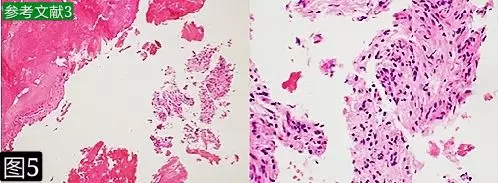

③活检病理检查表现为慢性、低毒、非特异性骨髓炎(图5);

活检表现为硬化性皮质骨片伴纤维组织和骨髓间隙的一些炎性细胞浸润(苏木精-伊红染色:(a,左)x100倍,(b,右)x400倍。

备注:穿刺活检虽然方便快捷,但是具有穿刺组织有限,有可能穿刺到炎性细胞浸润的坏死区或肿瘤外周区的局限性,所以必须切开活检才能明确排除。